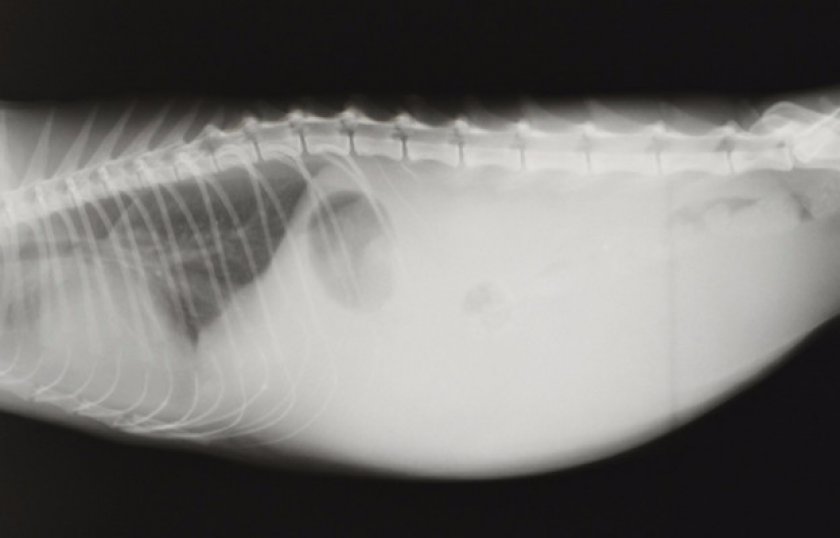

Экссудативный («мокрый») сценарий связан с выработкой и выходом значительного объема жидкости, поступающей в брюшную или грудную полость. Заметить этот процесс просто:

- также может увеличиться живот; в тяжелых случаях туда может попасть до 1 литра экссудата;

Стандартное осложнение — скопление в районе брюха или грудной клетки вязкой прозрачной жидкости, иногда с видимыми хлопьями и фибриновой нитью.

- Практикуется и пункция живота с последующим анализом взятой жидкости.